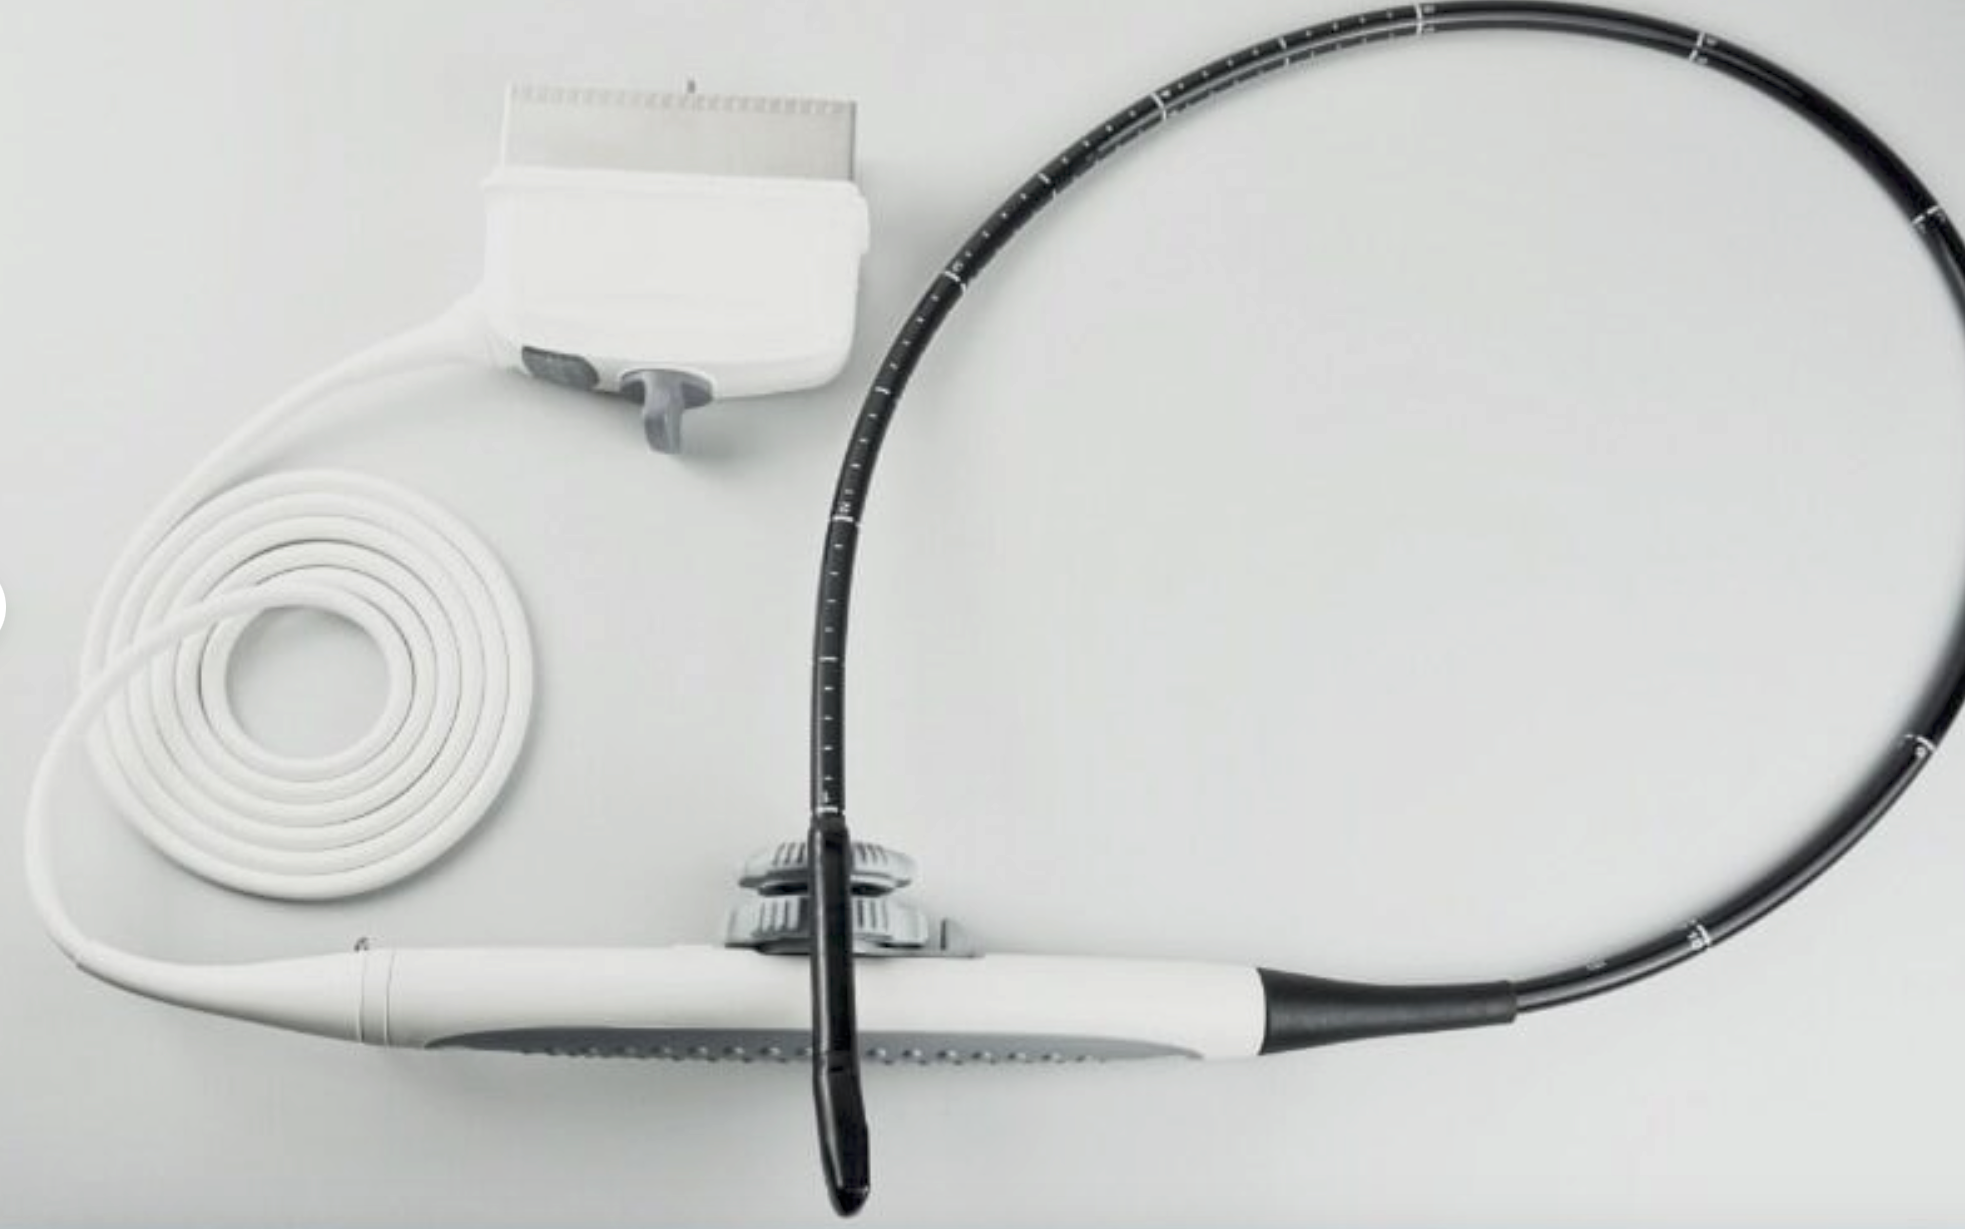

The Ultrasound probe SIEMENS Acuson 4C1 employs cutting-edge imaging technology to provide high-resolution images that enhance diagnostic capabilities. It uses a linear array transducer, which allows it to capture detailed anatomical structures in real-time. This technology improves the clarity of the images, making it easier for healthcare professionals to identify and assess various conditions. Because of its advanced features, this probe is indispensable in ultrasound examinations.

The SIEMENS Acuson 4C1 is designed with ease of use in mind. It features an ergonomic design that allows for comfortable handling during procedures. Additionally, the probe connects seamlessly to SIEMENS ultrasound systems, ensuring smooth operation. This compatibility streamlines workflow in a clinical setting, as healthcare providers can easily transition between different imaging tasks. Therefore, its user-friendly nature contributes to efficiency in the medical workplace.